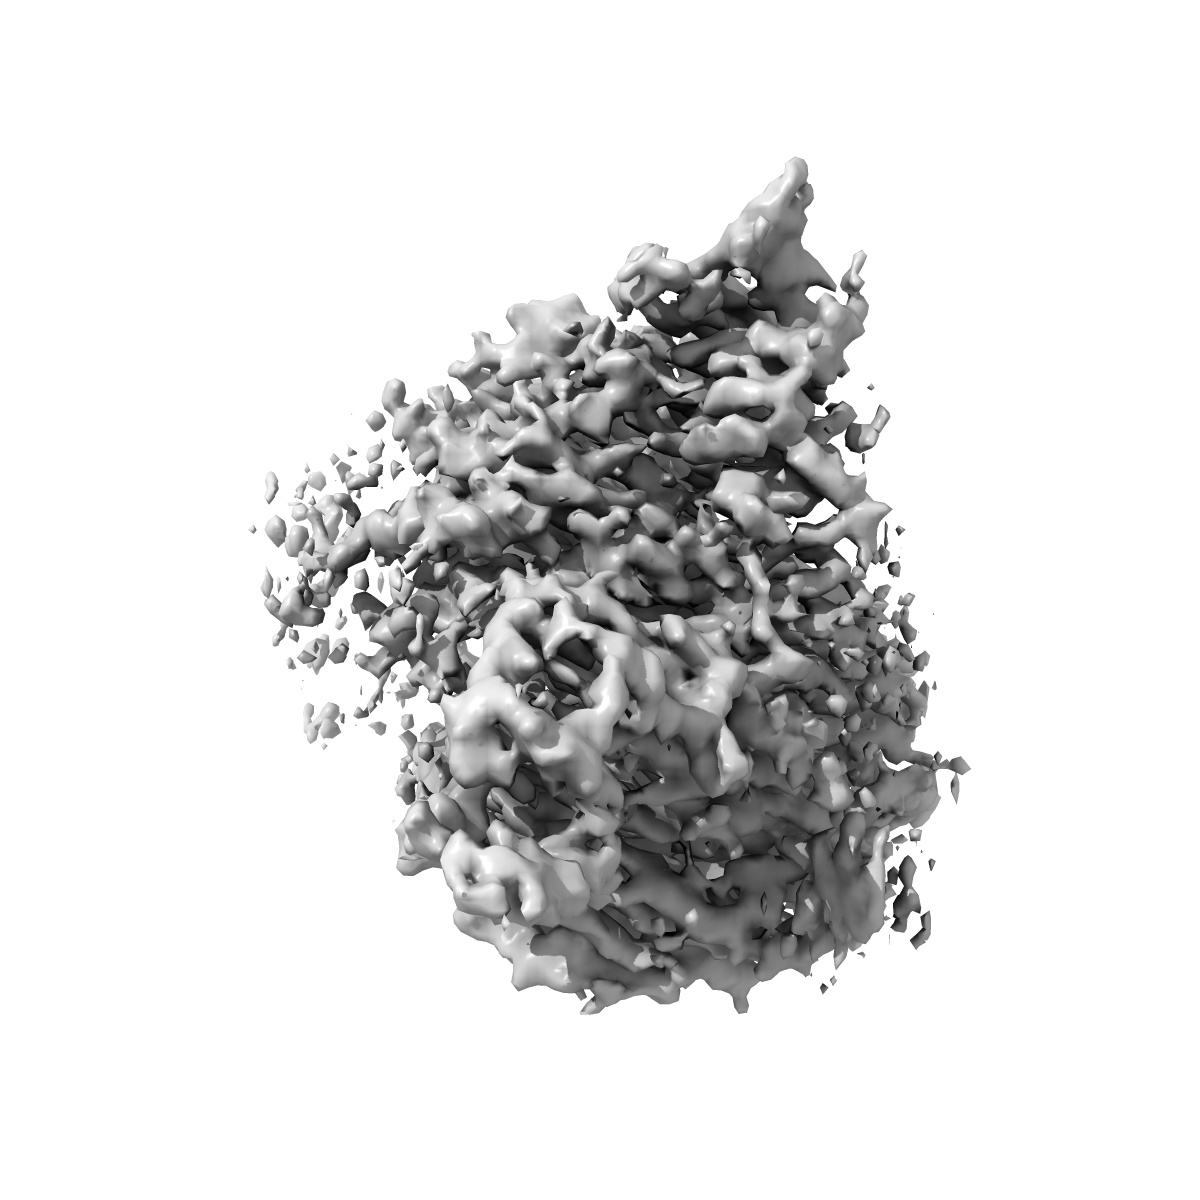

Cryo-EM structure of p110alpha in complex with p85alpha inhibited by BYL-719

Single-particle2.92 Å

Sample: Heterodimer of p110alpha with p85alpha

Cryo-EM structures of PI3K alpha reveal conformational changes during inhibition and activation.